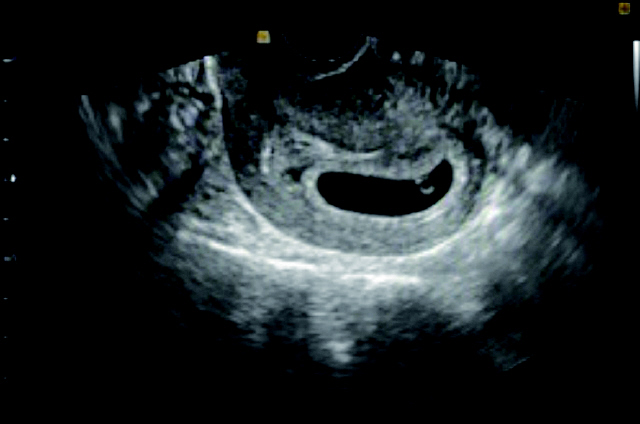

임신 6주차 초음파 사진. 여름이(태명)의 존재가 처음으로 밝혀진 날. 송채경화 기자